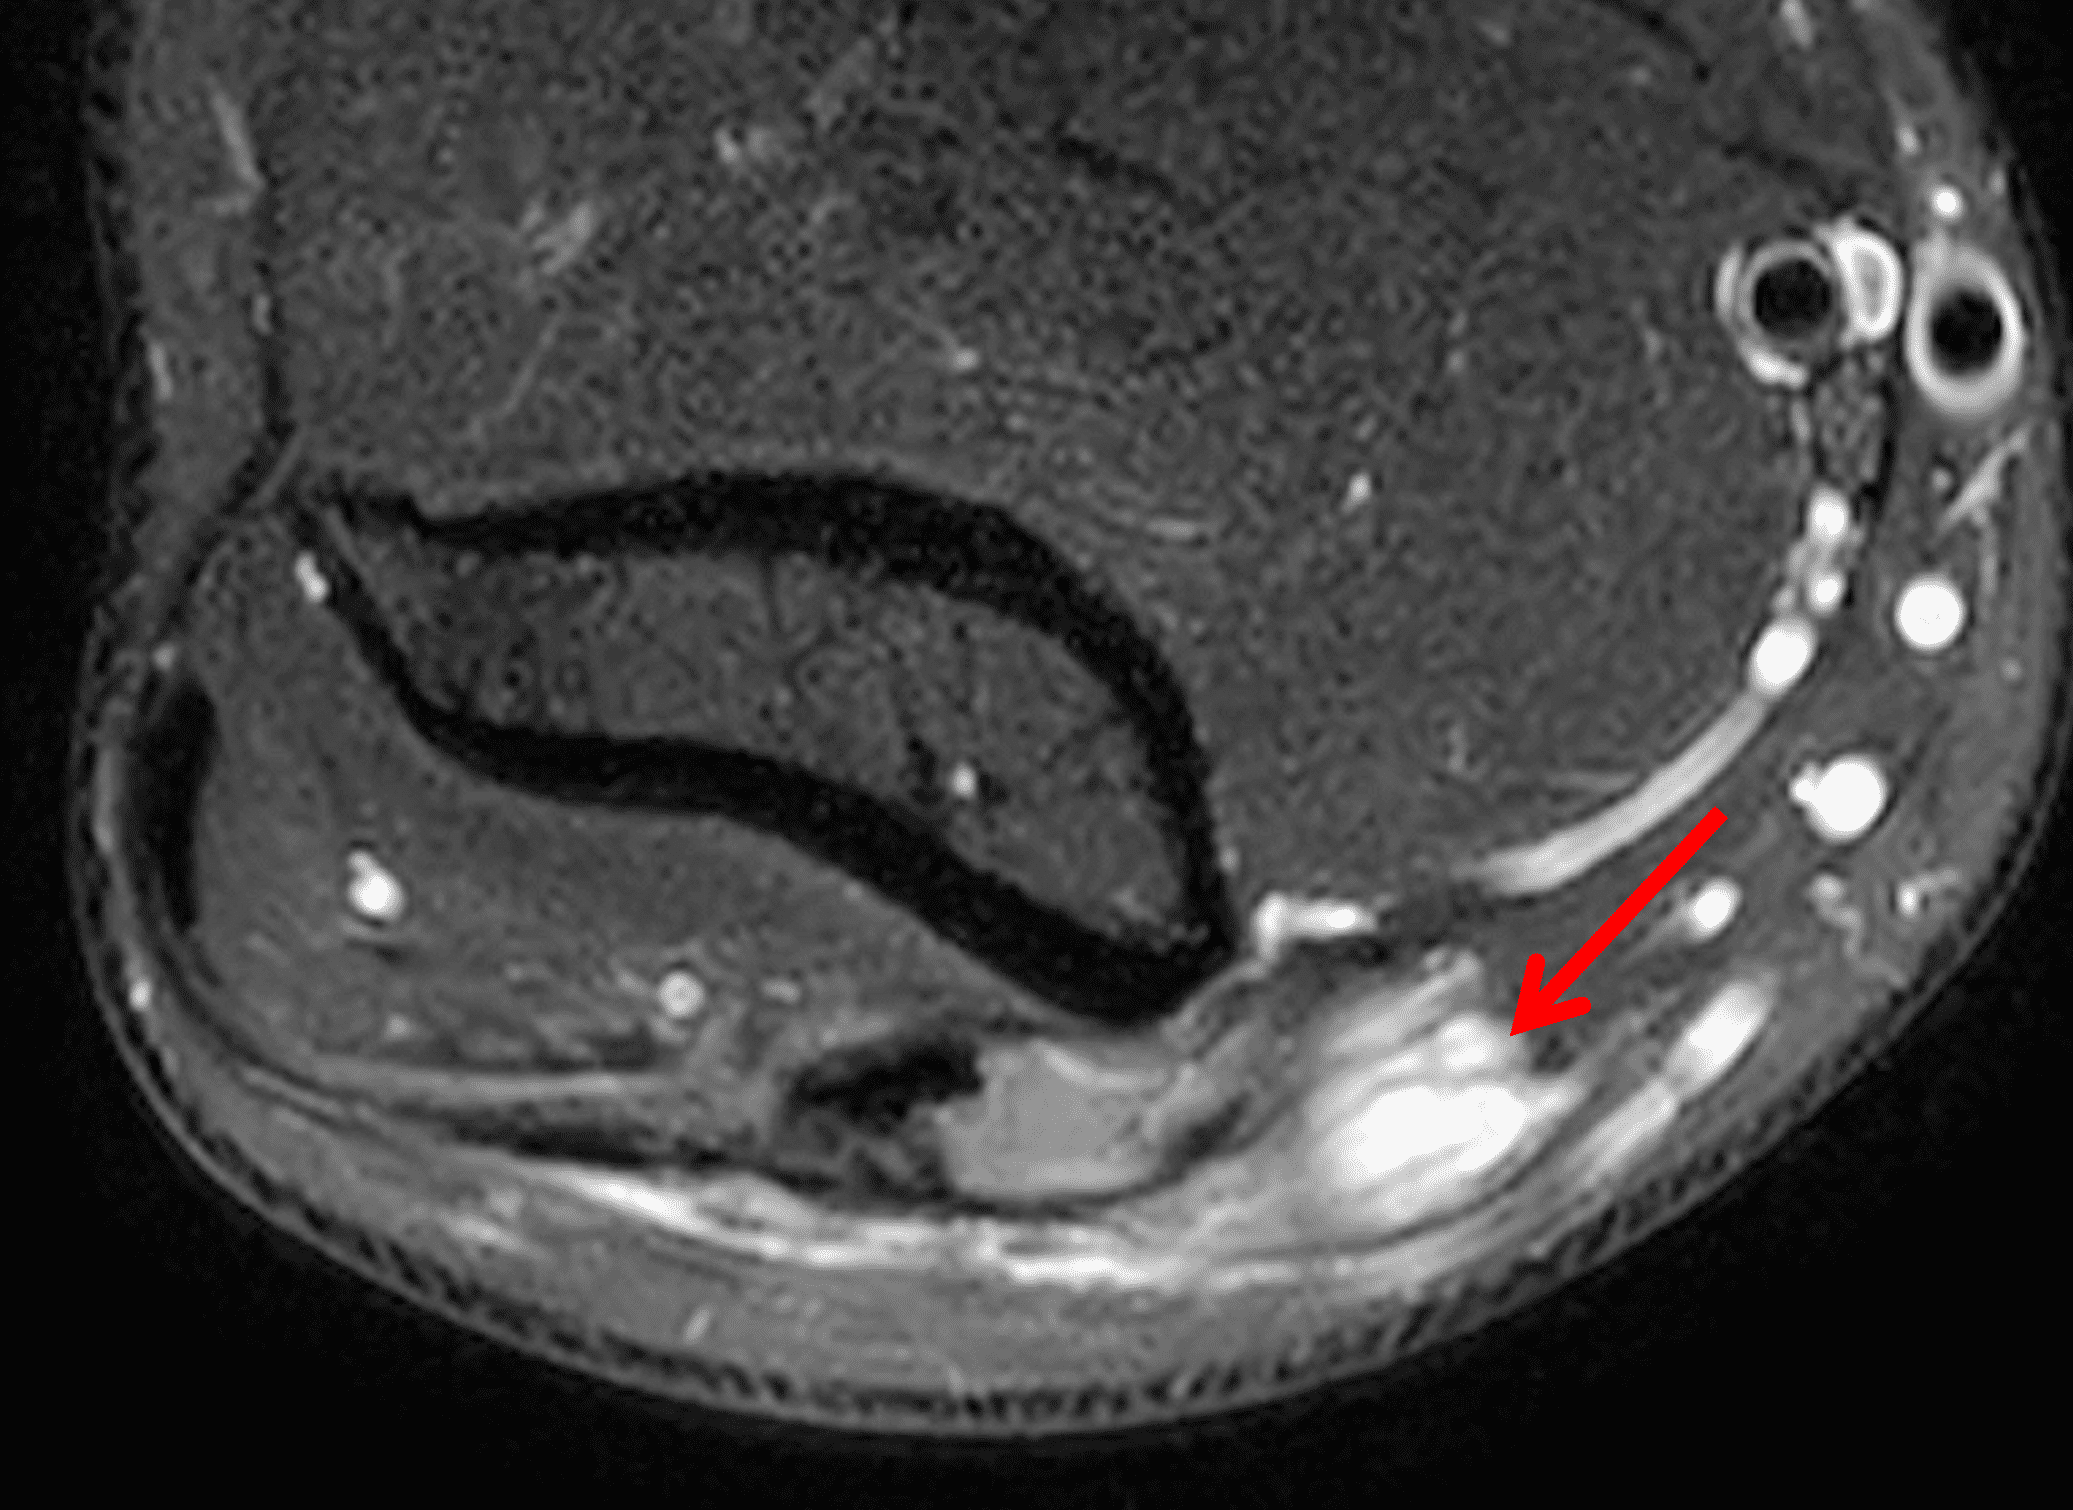

Figure 2: At the level of the cubital tunnel (2A and 2C), identifiable by the thin cubital tunnel retinaculum (yellow arrow), the ulnar nerve (red arrow) is focally enlarged and hyperintense compared to the nerve more distally (2B and 2D), where it lies between the two heads of the flexor carpi ulnaris muscle (asterisks). No soft tissue mass is present.